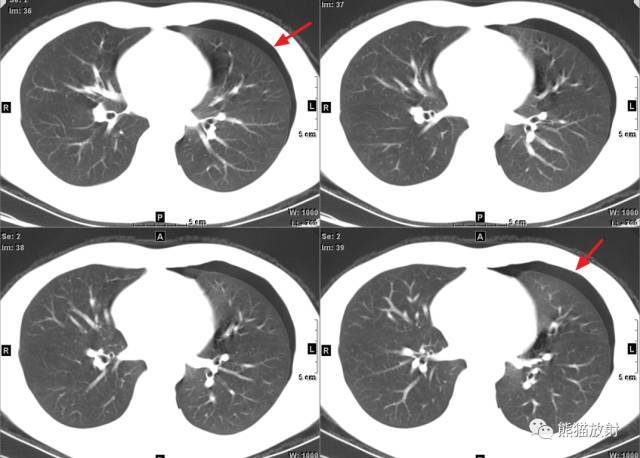

左侧气胸(肺被压缩约20%):

X线正位:左侧胸腔可见移位的胸膜线影 , 其外侧为条带状无纹理区 , 宽度小于患侧胸廓的1/4 。 左肺略受压 。

胸部CT:左侧胸腔游离气体 , 表现为胸顶部及外缘可见弧形无纹理低密度区 , 左上肺略受压 , 未见明显异常密度 。